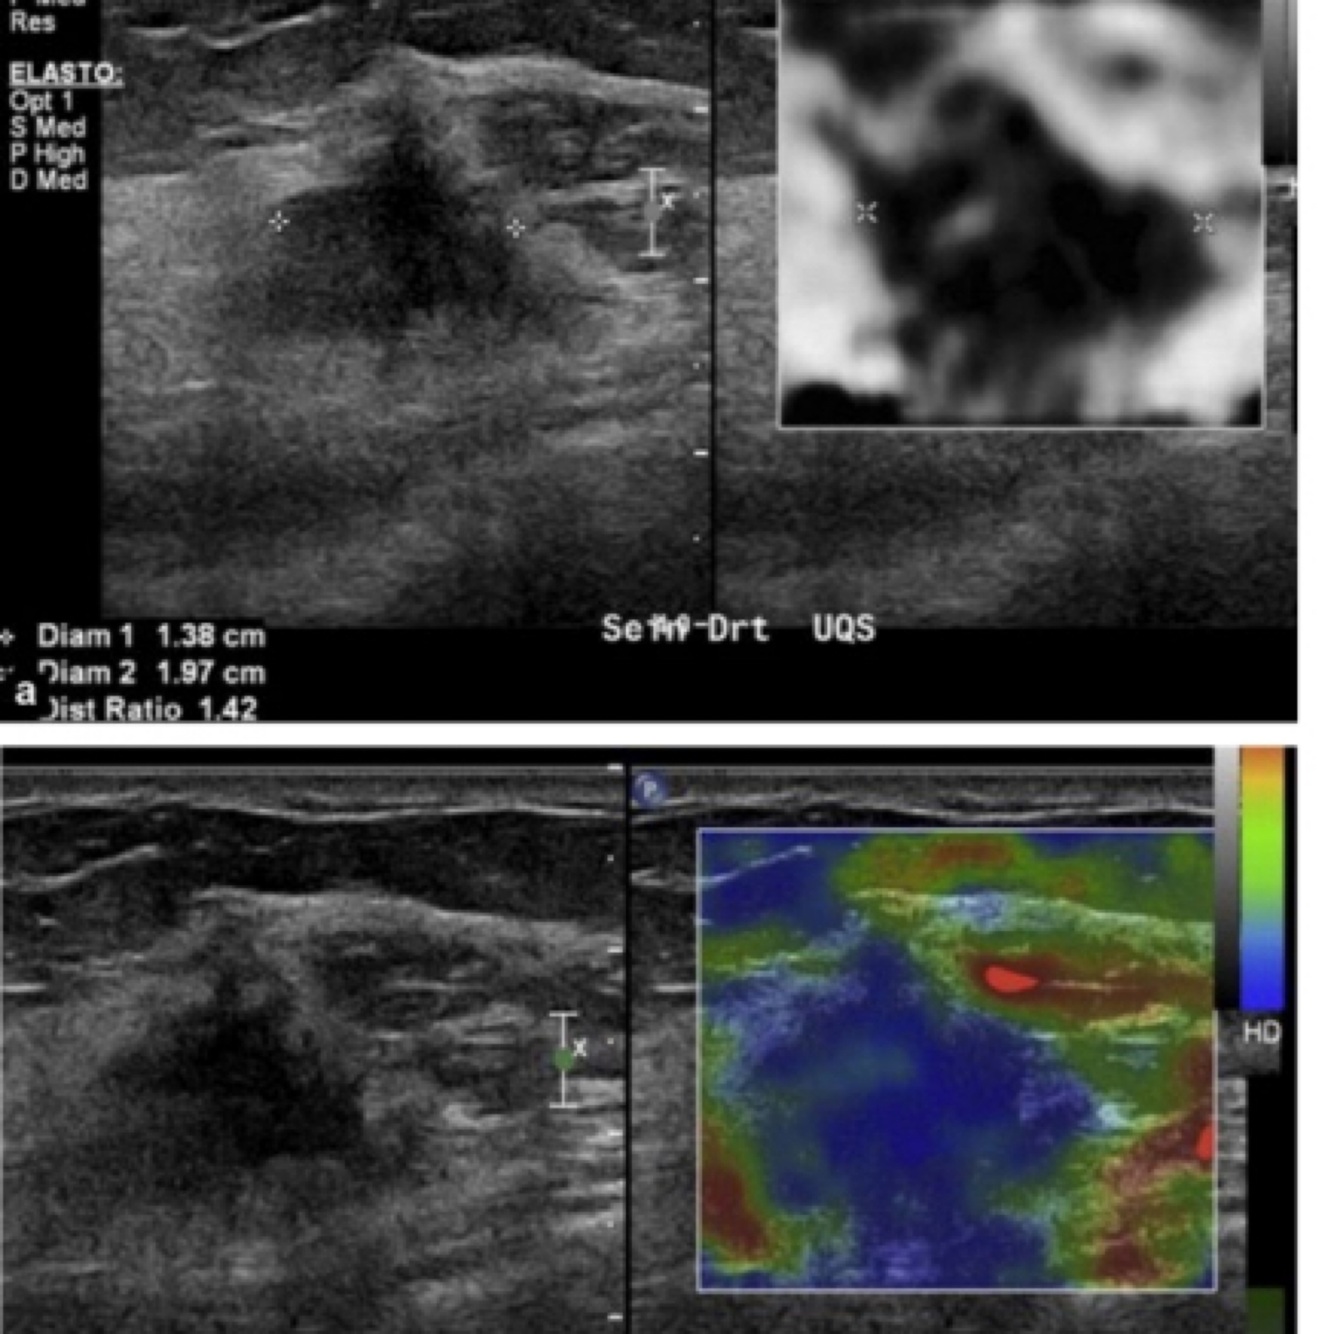

What does this image demonstrate?

A

Colour maps/ Contrast with static Elastography